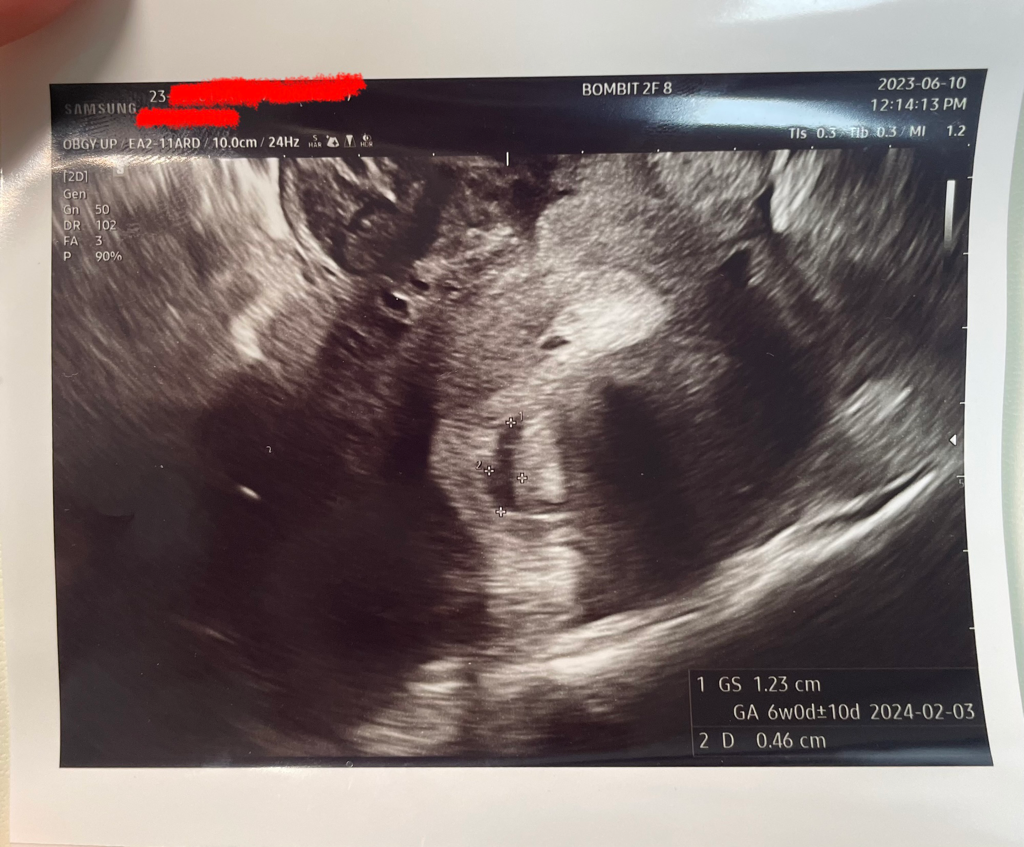

• 2번 째 사진

아기집은 표시해 드린 부분이며, 일반적으로 임신확인서는 태아 심박동이 확인되면 작성해드립니다.